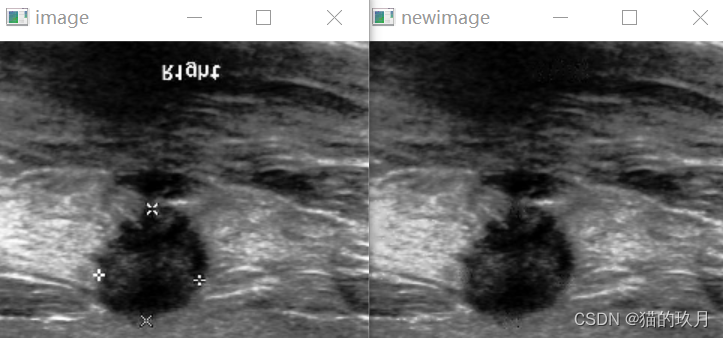

1.效果展示